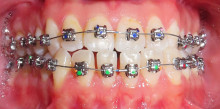

Kieferorthopädische Miniimplantate sind temporäre Implantate, die zur skelettalen Verankerung in den Kieferknochen eingesetzt und nach ihrem Einsatz...

Kieferorthopädische Miniimplantate sind temporäre Implantate, die zur skelettalen Verankerung...